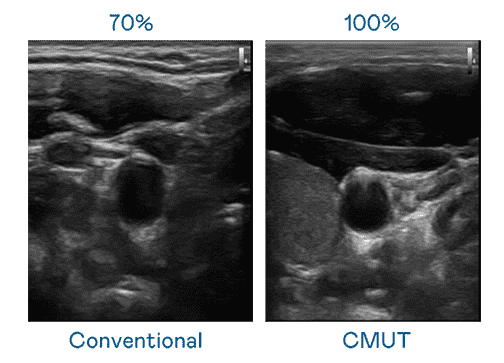

CMUT 技术是一种用电容式微机电元件来产生超音波讯号的技术。。与传统 PZT 压电式技术相比,,,,CMUT 频宽增加 30%,,,,更宽频的超音波讯号让影像解析度大幅提升,,,,是实现高影像品质医疗超音波扫描、、、促进精准医疗发展的关键技术。。。

大频宽带来超清晰影像

超音波影像的解析度高低,,,,首先取决于探头能发出的讯号频宽。。。。CG电子 CMUT 可提供高清晰的超音波讯号,,,,提供高频宽、、高灵敏度、、影像纹理细节更高的超音波影像,,,,协助医护人员缩短影像判读时间及利用精准的医疗影像进行诊断。。。